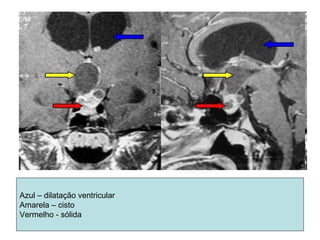

Azul – dilatação ventricular

Amarela – cisto

Vermelho - sólida

Astrocitoma cerebelar(imagem)

• TC

– 3 padrões

• Grande cisto tumoral com nódulo mural sólido

• Tumor sólido com áreas císticas

• Tumor cístico circundado por lesão sólida

– IV ventrículo desviado

– A. fibrilar – lesão hipodensa, homogênea, com pouco

edema perilesional, sem captação de contraste.

Calcificações – 10 a 20%

– A. anaplásico – lesão heterogênea, com captação

irregular de contraste

• RM

– Massa bem definida

– Hipointensas em T1; hiperintensa em T2